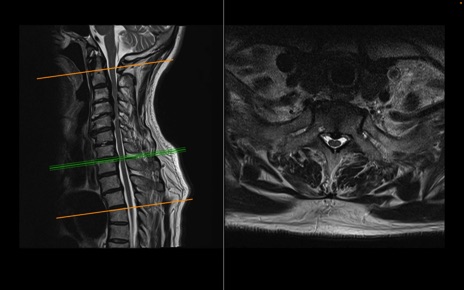

頚椎MRI

T2WI(横断像)

T2WI(矢状断像)